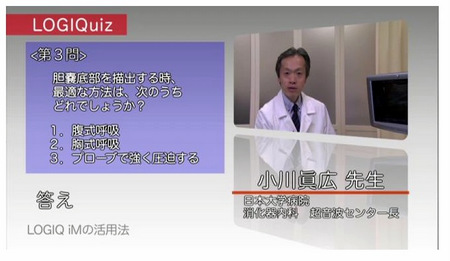

■LOGIQuiz(ロジックイズ)

同社製品の使い方をクイズ形式でわかりやすく紹介するコーナー。